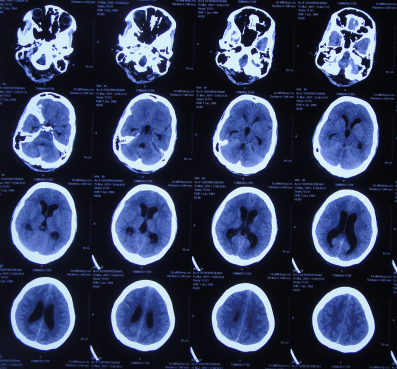

一、李小勇脑脊液科入院前病史

患者2019年2月初,因数次出现发作性黑蒙,2019年2月10日就诊于当地的河南省永城市某医院,查头颅CT未见明显异常(图-1);次日再查头颅核磁、颈椎核磁(图-2、图-3)后发现小脑扁桃体下疝畸形合并脊髓空洞。

图-1:2019年2月10日头颅CT